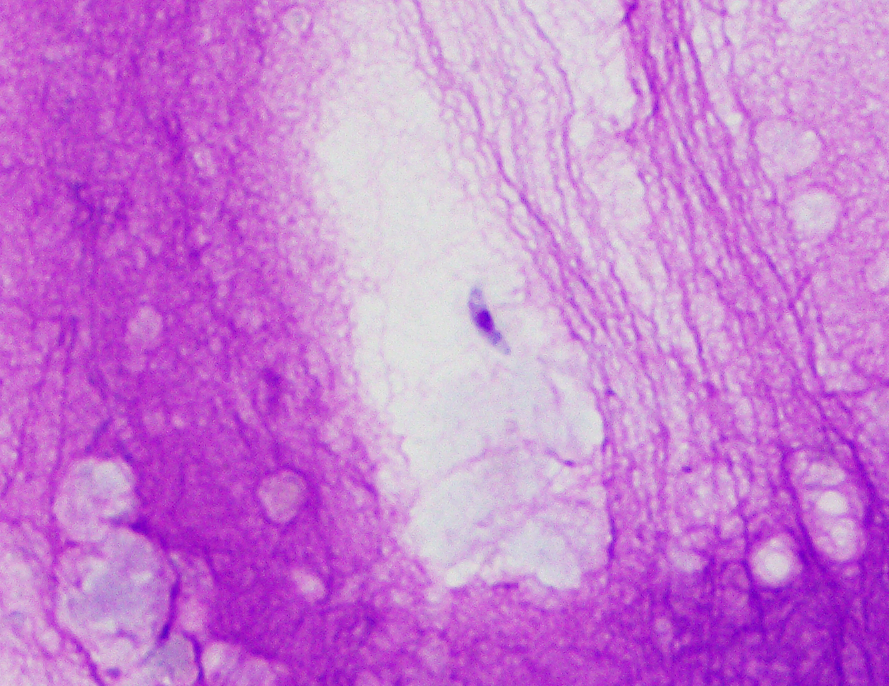

During the abdominal ultrasound, fine needle aspiration of bile and biopsy of liver parenchyma is performed. Results are shown: